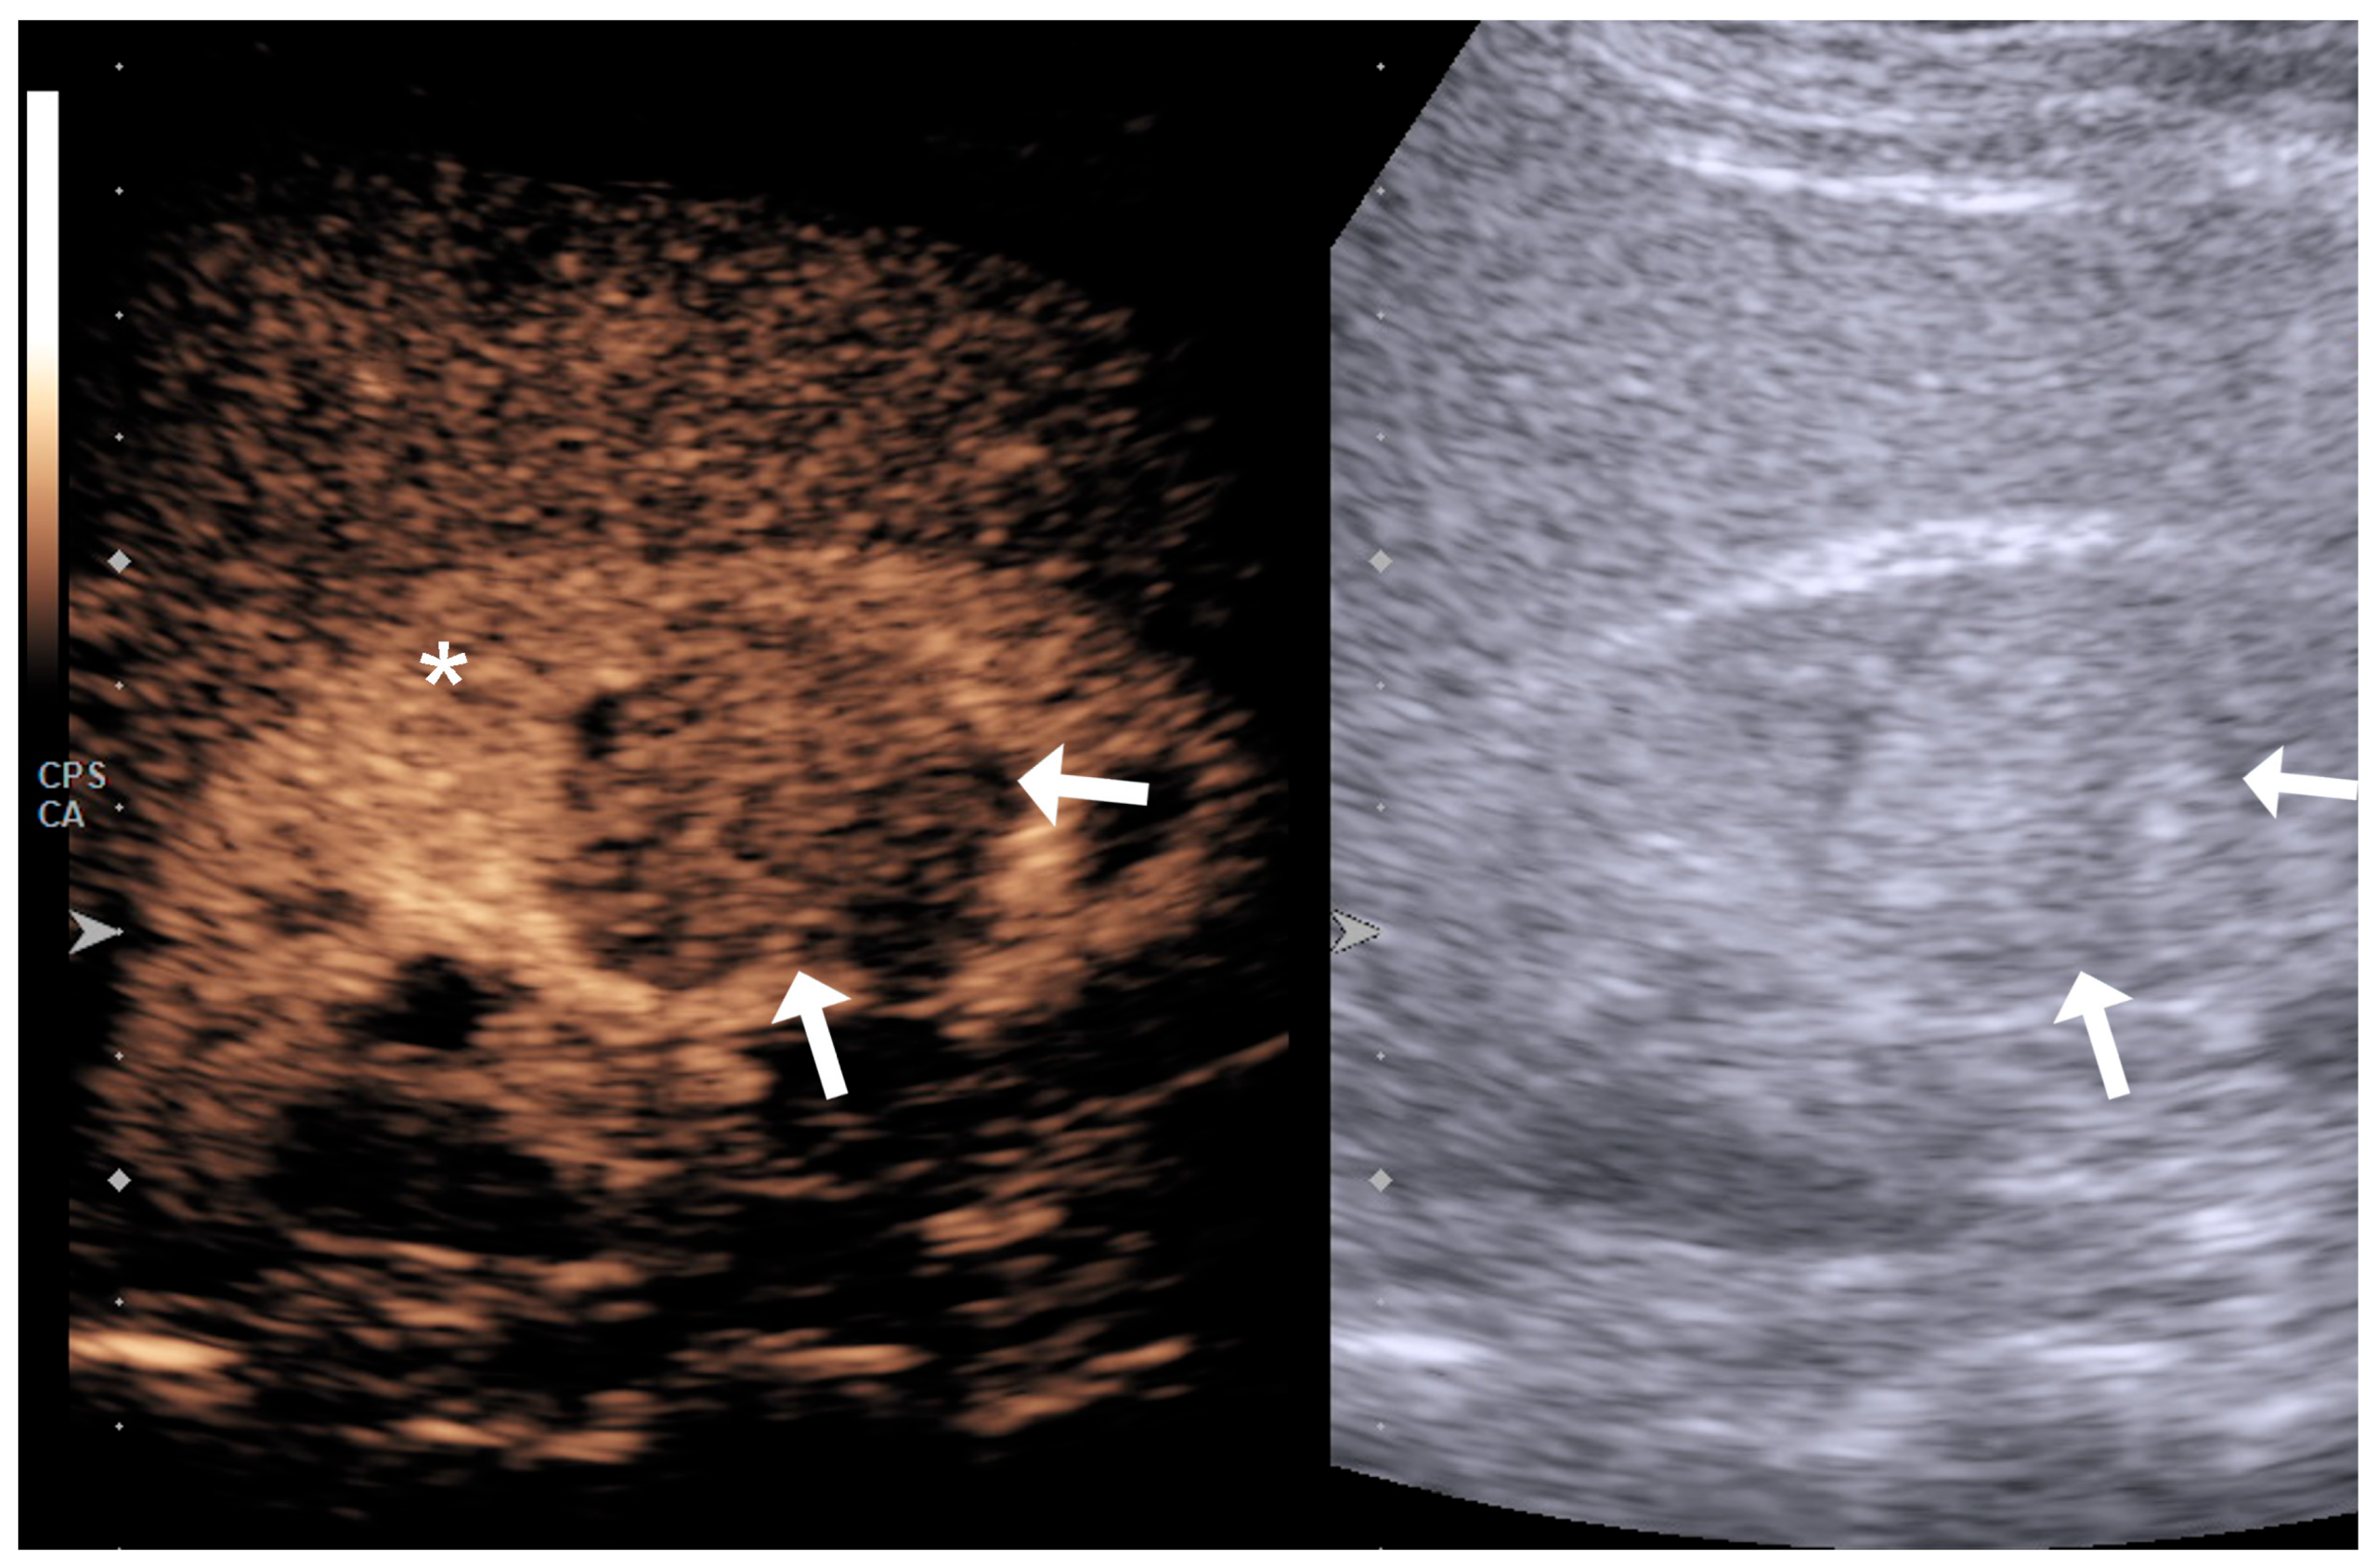

4.1. Qualitative Evaluation